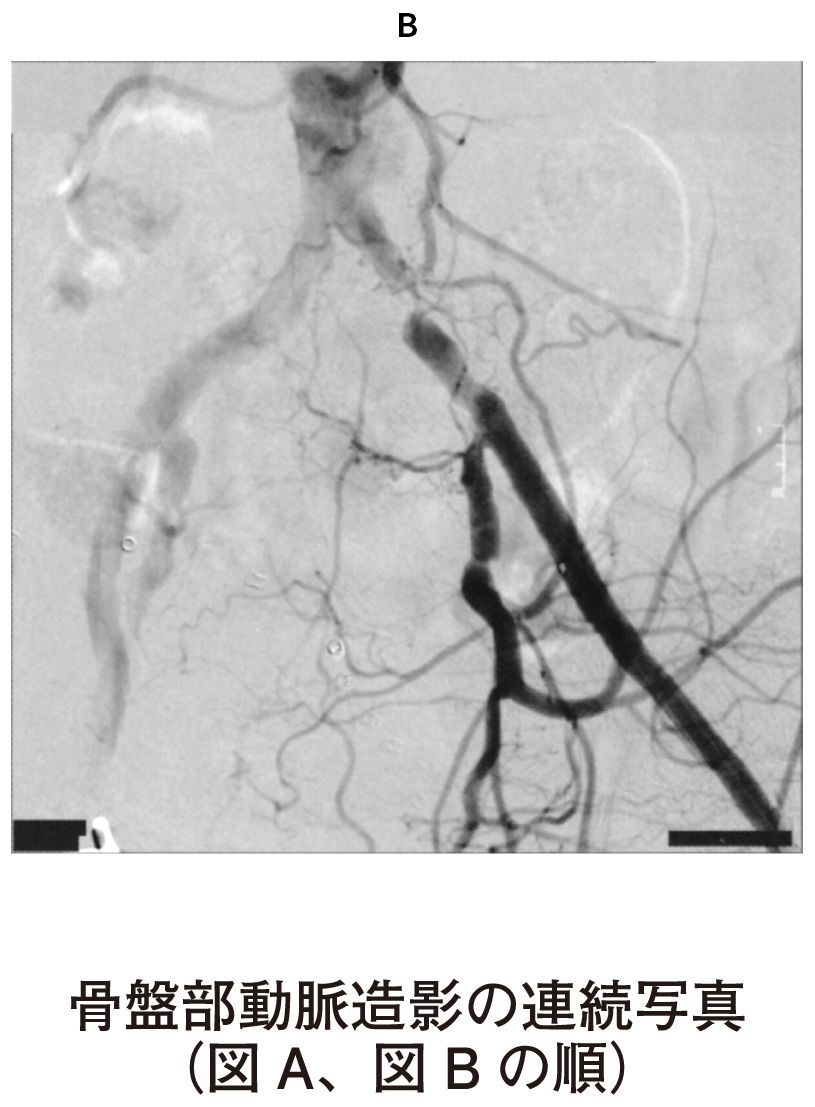

78歳の男性。歩行時の左下肢疼痛を主訴に来院した。4か月前から約300mの歩行で左下肢の痛みを自覚するようになり,立ち止まって休憩すると消失していた。最近痛みのため徐々に歩行可能距離が短くなった。60歳時から糖尿病と脂質異常症に対して定期的な投薬治療が行われている。喫煙は20歳から60歳まで20本/日。飲酒は機会飲酒。意識は清明。身長168cm,体重65kg。体温36.2℃。脈拍80/分,整。右上肢血圧160/90mmHg。呼吸数20/分。SpO2 96%(room air)。足関節上腕血圧比〈ABI〉は右側で0.96,左側で0.68であった。左大腿動脈から逆行性に造影した骨盤部の動脈造影の連続写真(A)(B)を下に示す。

研修医:「③左総腸骨動脈だと思います」